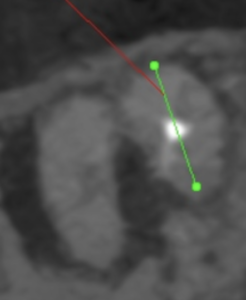

Pre-op CBCT(2024.11.25)

MB

P根以外のMB,DBには根尖病変がありSinus tractがある。

ということは…

MB+DB Apicoectomyだ。